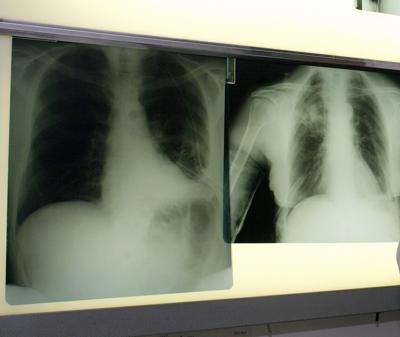

Arriva la ‘bomba intelligente’ contro il tumore al polmone

Una ‘bomba intelligente’, un nuovo farmaco a bersaglio molecolare, sbarra la strada al cancro del polmone che colpisce i non fumatori. E’ quanto emerge da…